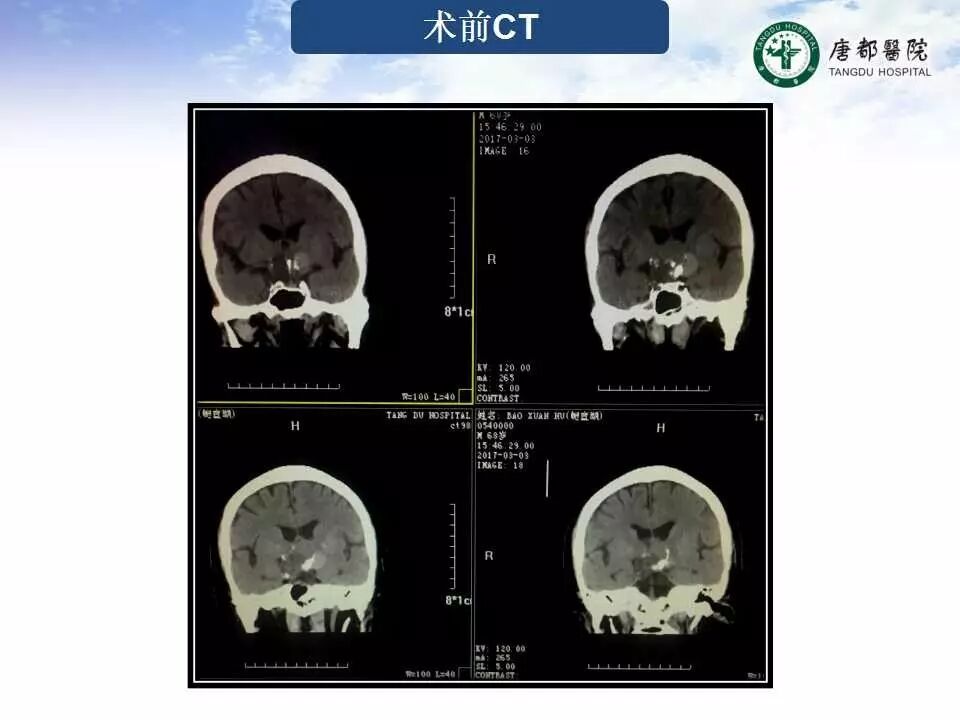

Case 2